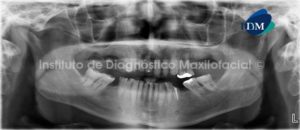

Paciente masculino de 15 años de edad que es referido por presentar alteración morfológica de las estructuras blandas y duras del sector anterior de los maxilares superiores. A la evaluación de la radiografía panorámica se observan defectos óseos (uno a cada lado distal de los incisivos centrales) que se extienden desde la cima del reborde alveolar hasta el piso de fosa nasal, comprometiendo este último (flechas rojas). Así mismo, se evidencia que los defectos óseos se encuentran asociados a la ausencia de las piezas 12 y 22; así como, a la presencia de dos piezas supernumerarias (flechas amarillas). Signos radiográficos compatibles con Paladar Fisurado Bilateral (Fig. 1).